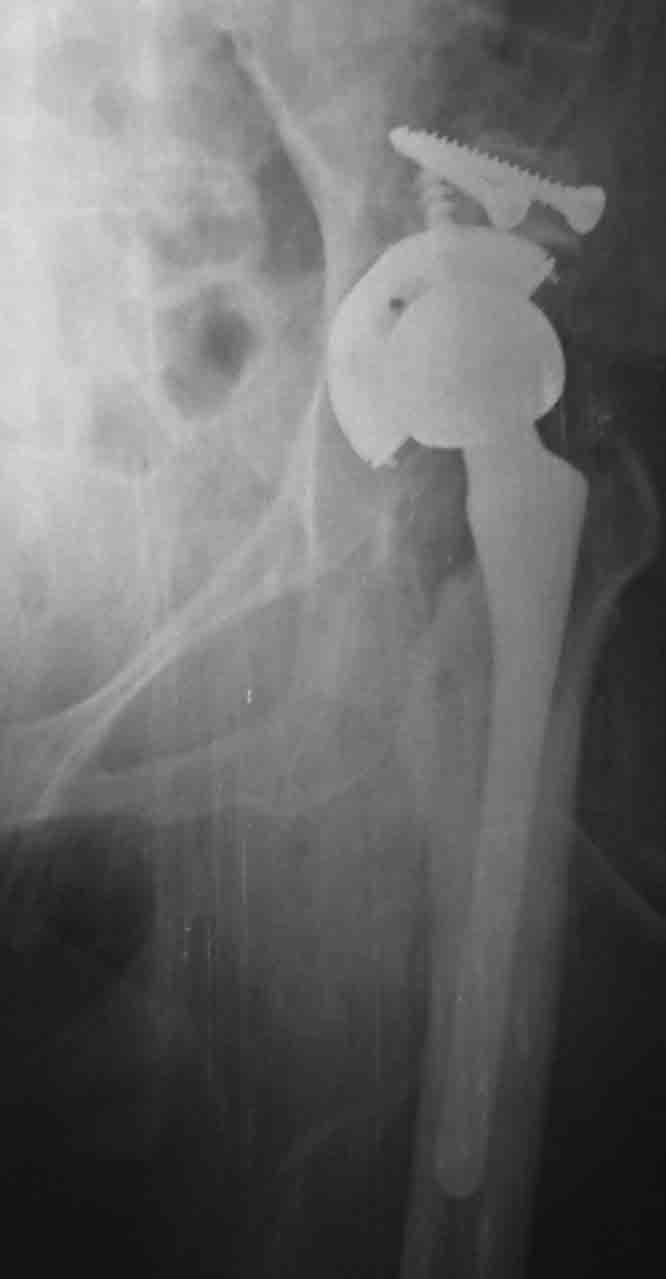

采用切除的股骨头做植骨

髋臼假体应安置在真臼内.若新臼包容不足70%,在骨质厚度允许的情况下应该继续加深研磨.可以采用切除的股骨头做植骨。

用螺丝钉把采用切除的股骨头做植骨固定在髋臼上缘

固定好骨块后用髋臼锉磨造加深髋臼

安装生物髋臼

安装好的髋臼和金属人工股骨头

图7. 手术后的照片 |